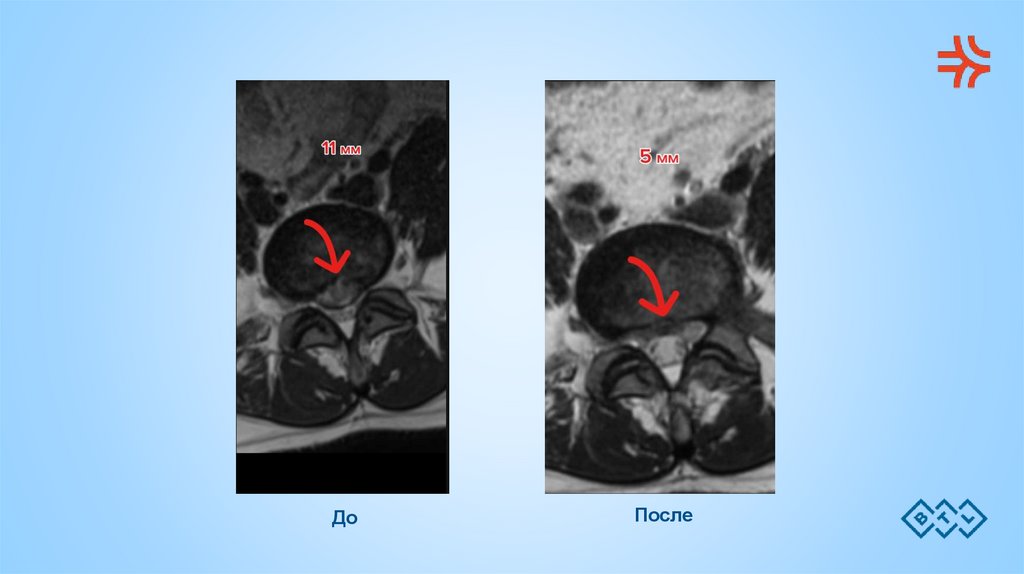

До

После